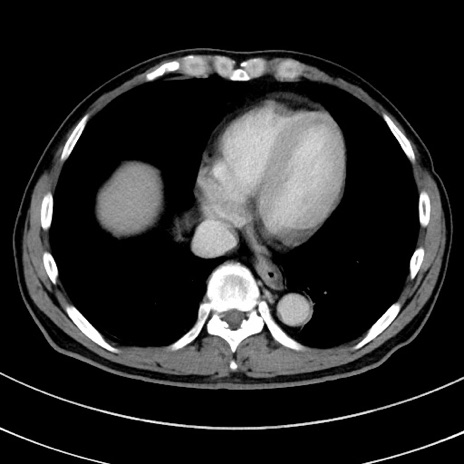

症例8(横断像)

【症例】 60歳代男性

【主訴】 黒色吐物

【現病歴】 4日前から嘔気自覚、2日前の朝食後にも嘔気あり、自分で手で嘔吐反射起こし嘔吐したところ血が混ざっていたため受診。

【既往歴】 5年前汎発性腹膜炎を伴う急性虫垂炎で手術、高血圧、前立腺肥大症、高脂血症

【身体所見】 腹部正中に手術癩痕あり 腹部平坦・軟圧痛なし膨満感あり

【データ】WBC 8400、CRP 4.54